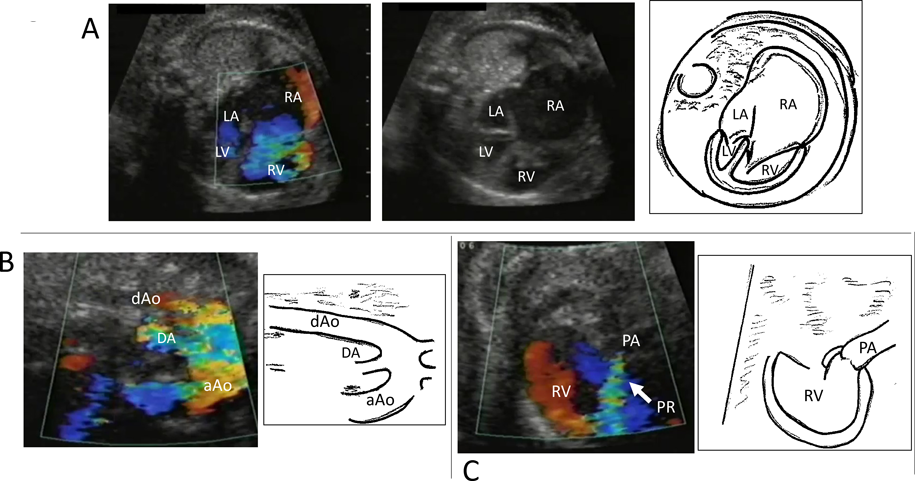

10. 左心低形成症候群(Hypoplastic Left Heart Syndrome: HLHS)

HLHSは,左室と上行大動脈の著しい低形成を認めることから胎児診断されることが多い.重症度の評価としては,主心室となる右室からの三尖弁逆流の有無と程度を確認し,上行大動脈の太さ・大動脈縮窄合併の有無の確認も必要である23).また卵円孔狭小化の評価が重要で,肺動脈血流パターンからも出生後の状態評価を推測できる24).具体的には3つの肺静脈血流パターンとして,A:連続性順行血流でわずかなa波逆行のみ(VTIR/VTIF ratio <or=0.18),B:連続性順行血流で増強したa波逆行(VTIR/VTIF ratio >or=0.18),C:短いto-and-fro血流,に分類した結果,Cは生後全例で卵円孔閉鎖,BはAより卵円孔が有意に狭小化していた(Fig. 8).このように胎児期早期より卵円孔狭小化による肺静脈うっ血パターンを呈する症例は生後肺の状態が悪く治療に難渋することが予想できる.